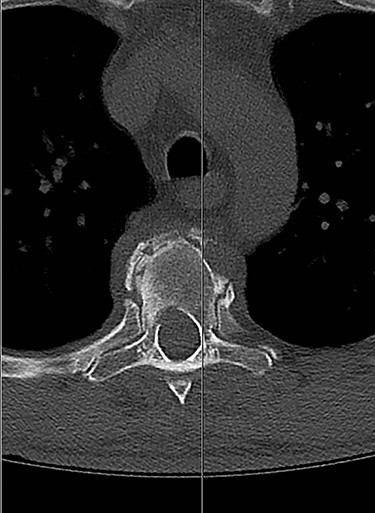

Spinal images are presented in Figs 1–6. Cross-sectional imaging revealed no other neoplastic lesion. He received dexamethasone 10 mg bolus then 4mg four times daily with appropriate proton pump inhibitor coverage. Due to no distinguishable major arterial feeder upon review of the imaging jointly with the neuroradiologist, pre-operative embolization was not attempted. The following morning, he underwent posterolateral right costotransversectomy, ligation of the ipsilateral T4 nerve root, T4 vertebrectomy and insertion of an expandable titanium cage with T1–T7 pedicle screw fixation (Figs 7 and 8). Post-operatively his pain improved to VAS 2/10 and motor power in his left lower limb improved to MRC grade 4/5. The patient was discharged home Day 10 post-admission with physiotherapy.

Sagittal computed tomography (CT) scan demonstrated multiple lytic lesions and pathological fracture of the T4 vertebra with almost complete collapse along with kyphotic deformity.